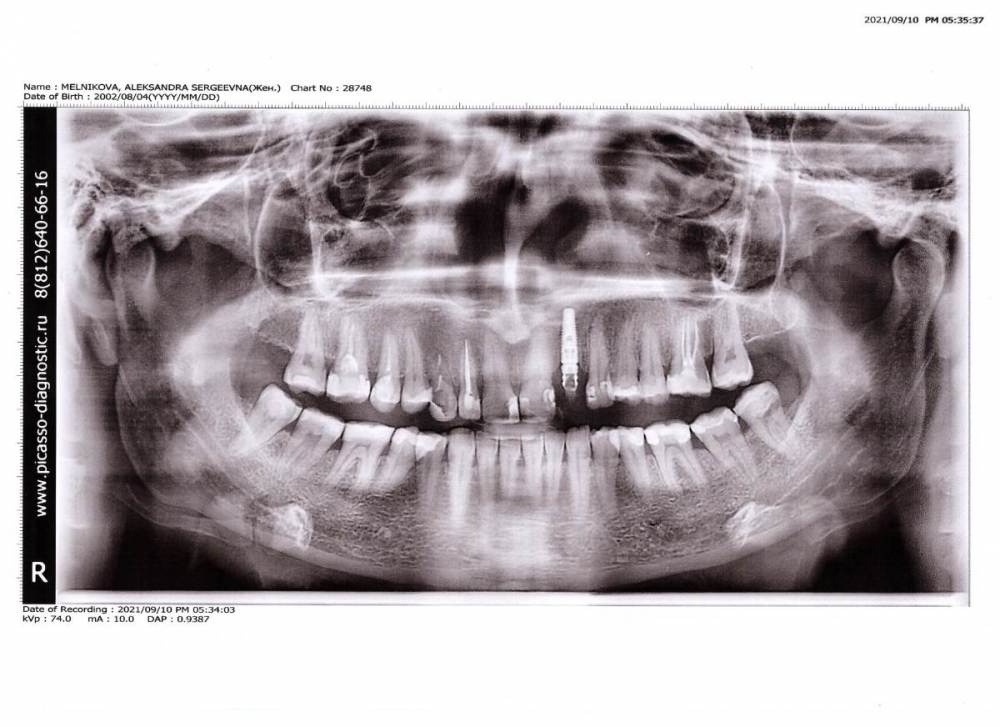

МОН Опубликовано 10 сентября, 2021 Поделиться Опубликовано 10 сентября, 2021 Добрый день. Нужна Ваша консультация. В начале ноября 2020 была сделана имплантация двойки сверху и установлена временная коронка. В июле появилось странное ощущение в небе, сейчас есть реакция на холодное/горячее, небольшое покалывание (пульсация) с внутренней стороны неба под имплантом. Была в понедельник (06.09.2021) у имплантолога, он сказал, что с имплантом все хорошо и можно ставить постоянную коронку. Сегодня сделала панорамный снимок челюсти, в районе тройки, четверки со стороны импланта костная ткань темнее. Подскажите, пожалуйста, все ли нормально с установленным имплантом? И из-за чего может быть потемнение в костной ткани (см.фото). Спасибо. Ссылка на комментарий

It'sGeorgy Опубликовано 10 сентября, 2021 Поделиться Опубликовано 10 сентября, 2021 4 часа назад, МОН сказал: Подскажите, пожалуйста, все ли нормально с установленным имплантом? Судя по этому снимку, все хорошо. 4 часа назад, МОН сказал: сейчас есть реакция на холодное/горячее, небольшое покалывание (пульсация) с внутренней стороны неба под имплантом Чтобы разобраться с этими жалобами необходимо, как минимум, КТ. В идеале - очный осмотр. 4 часа назад, МОН сказал: И из-за чего может быть потемнение в костной ткани (см.фото). Из-за того, что это кость. На разных участках челюсти она неоднородна и имеет разную плотность. 4 часа назад, МОН сказал: и можно ставить постоянную коронку. Я бы сначала проконсультировался с терапевтом по поводу пломбы на 2.1. Возможно, стоит ее поменять. 1 Ссылка на комментарий